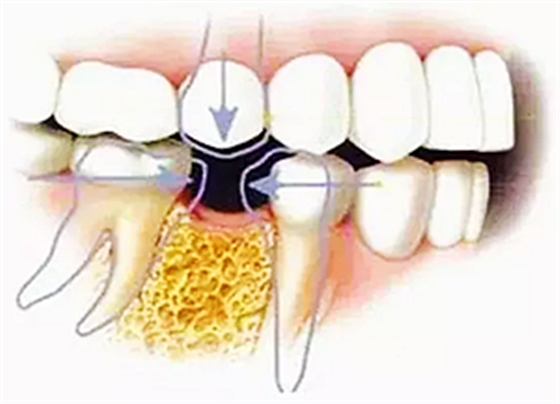

那你要說如果壞牙直接拔掉,不鑲牙不就好了?那我只能說No zuo No die!時間久了,兩邊的牙向缺牙的地方倒了,對應(yīng)的咬合面上的牙齒伸長了,這時候會發(fā)現(xiàn)缺牙附近前后左右的牙吃東西都塞牙,長期的塞牙造成其他牙齒的齲壞,開始了上述的循環(huán)。

這時候的治療費用不是一顆牙的問題,要乘上壞牙的數(shù)量,更貴了。繼續(xù)惡化下去,多顆后牙缺失(牙齒缺失多數(shù)從后牙開始)長期不鑲,只能用前邊牙吃飯,前邊牙承受不了咀嚼的力量,被磨耗變的很矮,咬合距離喪失,關(guān)節(jié)又發(fā)生問題,看關(guān)節(jié)病又是筆大花費,關(guān)鍵還不一定看的好...